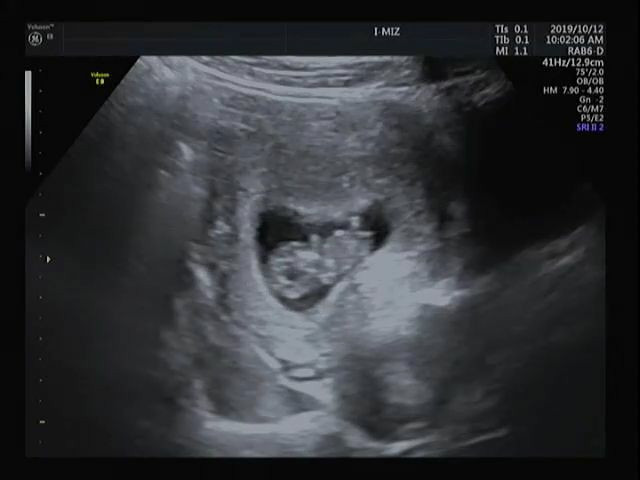

KakaoTalk_20200129_161316428.jpg 귀여운 9주 젤리곰시절, 시어머니가 병원을 데려다주셨다.

큰 이벤트없이 아이의 심장소리를 듣던 날,

초음파에서 반짝이는 것이 제 힘을 다해 움직이고 소리를 내는것을 보고

울컥하기보단 신기했다. 저 조그마한 몸에 심장이 다 있네.. 쿵쾅쿵쾅 건강하게 심장이

뛰는 모습을 보고 이후 젤리곰으로 그새 커져있는 모습도 보았다.

KakaoTalk_20200129_161316174.jpg 무언가 오밀조밀 예쁘게생긴 우리 아들내미